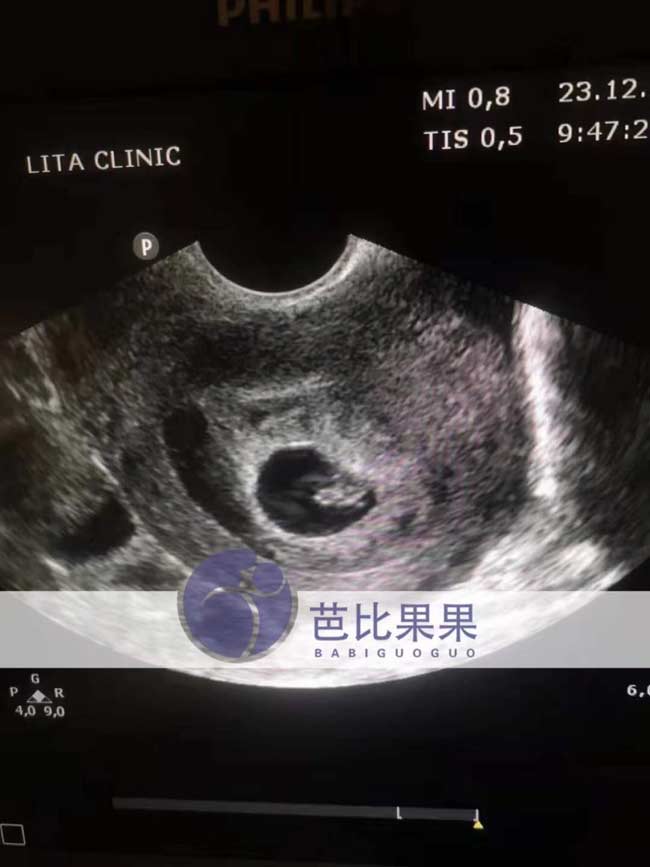

z女士的乌克兰试管验孕成功后首次B超检查

z女士家的乌克兰试管验孕成功后的首次B超检查,胚胎着床了,坐等报告翻译出来,期待中~